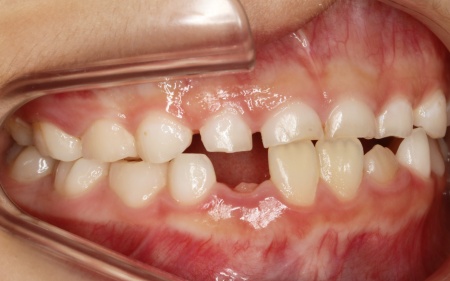

治療前

診断結果 拝見したところ、患者様は乳歯のみが生えている乳歯列期の段階でしたが、この時点ですでに反対咬合が認められました。

反対咬合とは、下の前歯が上の前歯よりも前に出ている状態のことで、一般的に「受け口」とも呼ばれます。